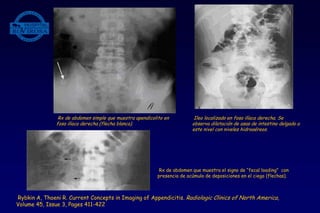

• Rx abdomen simple:

- Presencia de apendicolito

- Gas en cuadrante inferior derecho.

- Deformidad del gas del ciego y colon ascendente por presencia de una masa

inflamatoria a este nivel.

- Ileo localizado, con presencia de gas en ciego y resto del colon .

- Últimamente se ha descrito otro signo que sería de una alta especificidad y

sensibilidad en los casos de apendicitis que es la “carga fecal” en el ciego (fecal

loading) o acúmulo de deposiciones en la región cecal.

Rx de abdomen simple que muestra apendicolito en

fosa ilíaca derecha (flecha blanca).

Ileo localizado en fosa ilíaca derecha. Se

observa dilatación de asas de intestino delgado a

este nivel con niveles hidroaéreos.

Rx de abdomen que muestra el signo de “fecal loading” con

presencia de acúmulo de deposiciones en el ciego (flechas).